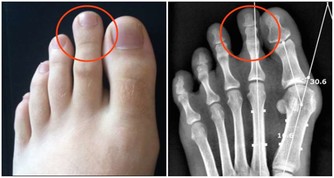

腎臟已經出現損傷,身體會有這幾個表現

3、晨起眼瞼或顏面水腫,下肢水腫,且按壓後凹陷部位無法馬上恢復。